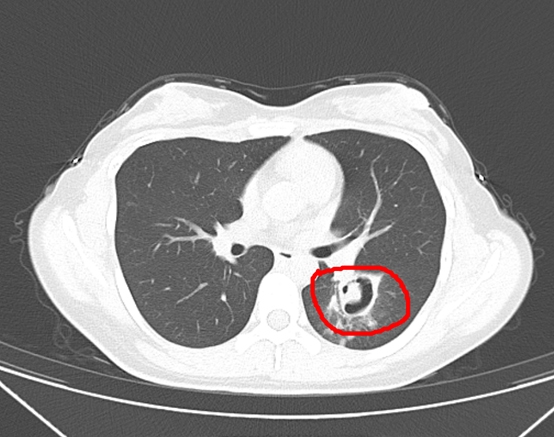

经过一系列检查,接诊的感染性疾病科(肝病科)周翔主任医师从肺部CT上发现,王女士的肺部长出了一个个“小树芽”,经过专家查看,怀疑是霉菌性肺炎。

了解了这一情况后,为了进一步确诊病情,周翔为王女士做了纤维支气管镜检查,果然发现气道壁上缀着大量白色菌斑。

经过化验分析,确认王女士感染的是曲霉菌,这是一种常见的霉菌。